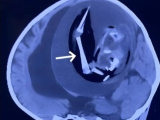

Hôm 21/10, tại Bệnh viện King’s College (London), bà trải qua ca phẫu thuật kéo dài 4 tiếng do Giáo sư Keyoumars Ashkan, chuyên gia phẫu thuật thần kinh hàng đầu nước Anh, trực tiếp thực hiện. Trong suốt quá trình phẫu thuật, bà Bacon hoàn toàn tỉnh táo dưới tác dụng của thuốc gây tê cục bộ, chỉ làm tê da đầu và xương sọ.

Ca phẫu thuật áp dụng phương pháp kích thích não sâu (Deep Brain Stimulation – DBS), trong đó các điện cực nhỏ được cấy vào vùng não kiểm soát vận động để giảm triệu chứng run, cứng và chậm vận động.

Giáo sư Ashkan cho biết: “Chúng tôi khoan hai lỗ nhỏ bằng nửa đồng xu 5 pence trên hộp sọ của Denise, sau đó gắn một khung định vị có toạ độ chính xác như hệ thống GPS để dẫn đường đến đúng vị trí trong não cần cấy điện cực. Khi kích hoạt dòng điện ở bán cầu trái, bàn tay phải của bà lập tức cử động linh hoạt hơn. Điều tương tự cũng xảy ra khi kích hoạt bên phải.”